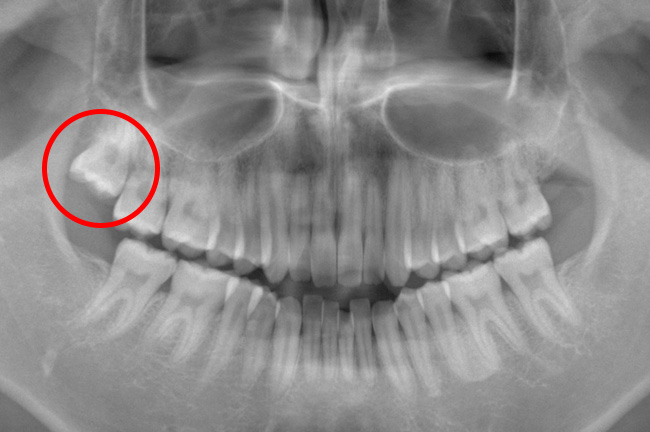

CASE 3

事前にCT撮影を行い神経との位置関係を確認して抜歯を行いました。

頬が被るように親知らずが生えており、歯ブラシが上手くできず虫歯になり歯石もたくさん付いていました。

痛み出血もほとんどありませんでした。

抜歯前

抜歯後

基本情報

| 年齢・性別 | 30代・女性 |

|---|---|

| 主訴 | 右下8/右下の親知らずが痛い |

| 治療内容 | 通常抜歯 |

| 治療期間 | 約30分 |

| 治療費 | 約4,000円 |

| リスク・副作用 | 2〜3日は腫れと痛みがある。 |